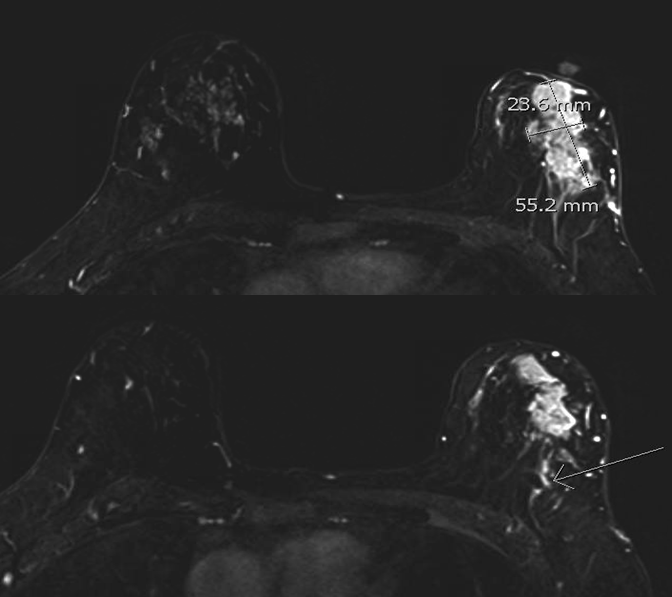

الحالة الثانية: اتضح وجود كتلة كبيرة في الصدر الأيمن بعد الفحص وعمل خزعة تحت الأشعة التلفزيونية ثم رنين مغناطيسي للصدر يوضح انتشارها. تم علاج المريضة وعمل رنين مغناطيسي يوضح صغر الكتلة بشكل كبير جدا ثم تم استئصال الثدي الأيسر بشكل كامل وترميمه جراحيا.

الحالة الأخيرة: كتلة صغيرة جدا في الثدي الأيسر. تم عمل رنين مغناطيسي واكتشاف انتشار للغدد اللمفاوية المجاورة. تم علاج المريضة واستئصال الكتلة والغدد بشكل كامل.